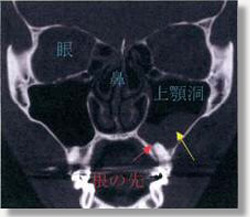

抜歯により上顎洞底に穴が開いた状態。口と鼻が交通する(黄色の矢印)